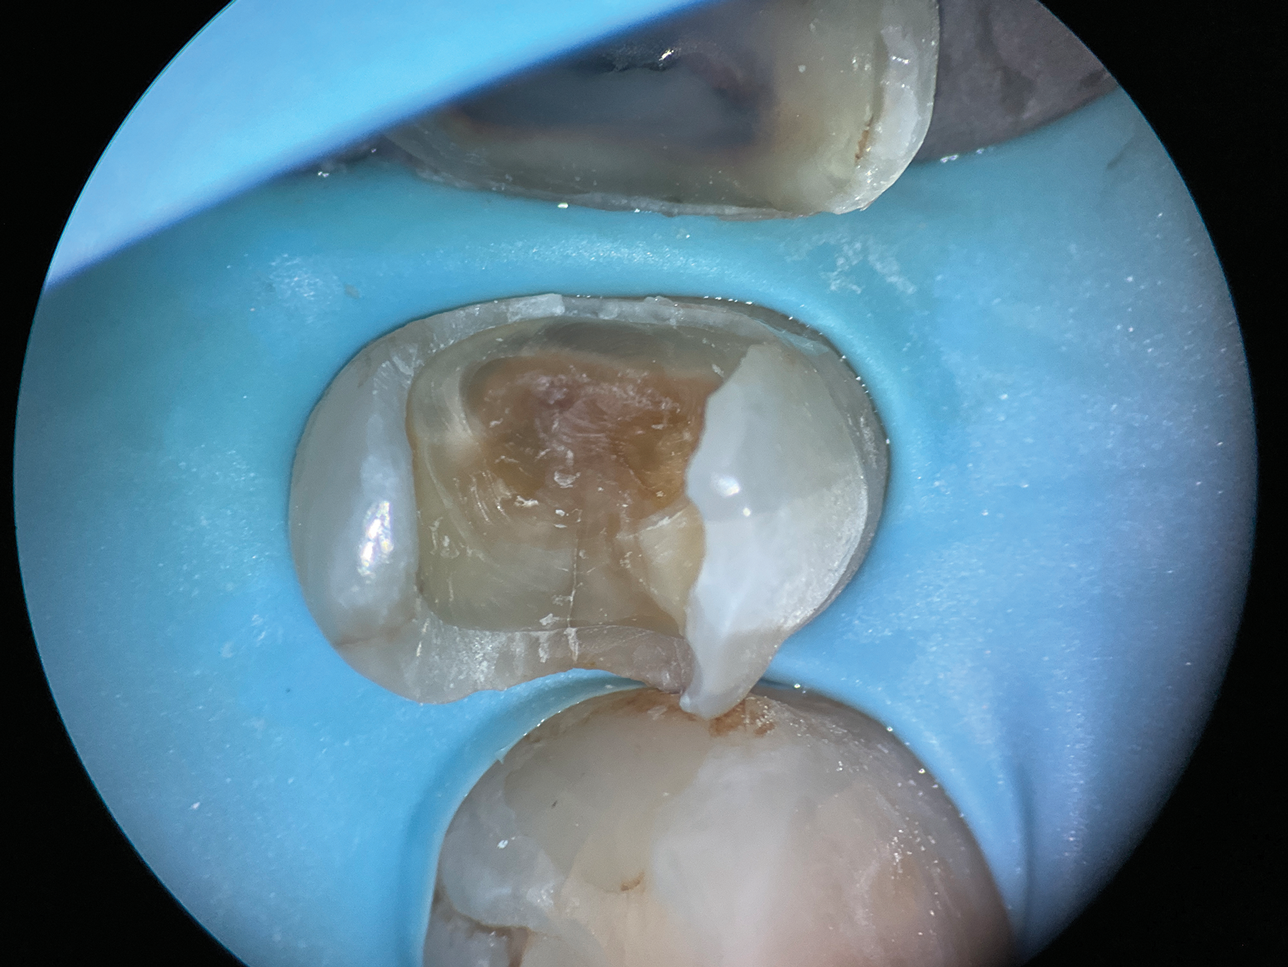

(12.) After subgingival placement of a Tofflemire matrix, despite using a wedge and adding additional support with polytetrafluoroethylene tape, fluid infiltration persists through the matrix and margin.

Figure 12

(13.) A wide 2-mil copper band was placed as an additional matrix to create absolute isolation, effectively sealing the space between the Tofflemire matrix and the margin.

Figure 13